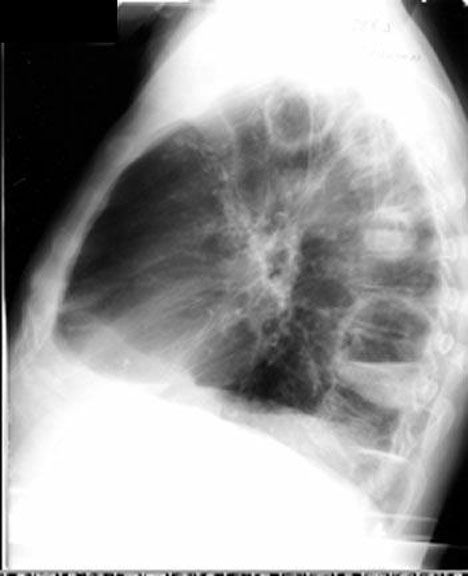

| CXR | ? lateral segment of RML ? Fluid in fisssure | Answer | |